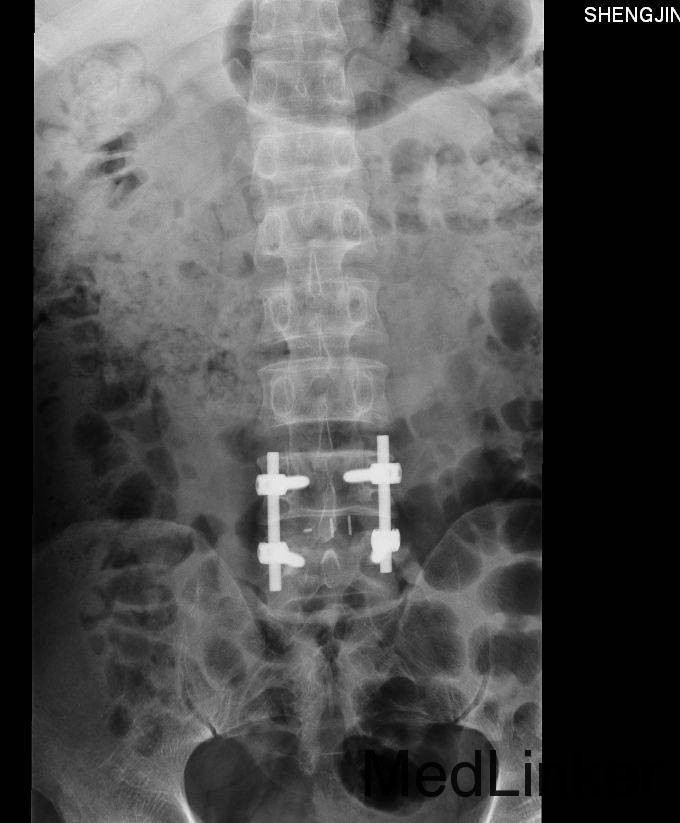

诊断 : 腰椎间盘脱出症,髓核游离 入院后完善检查,查无手术禁忌症后行腰椎后路椎板减压间盘切除椎间融合器椎弓根钉内固定术,术后患者左下肢疼痛缓解,术后支具保护下三天后拔除引流管后下地行走。